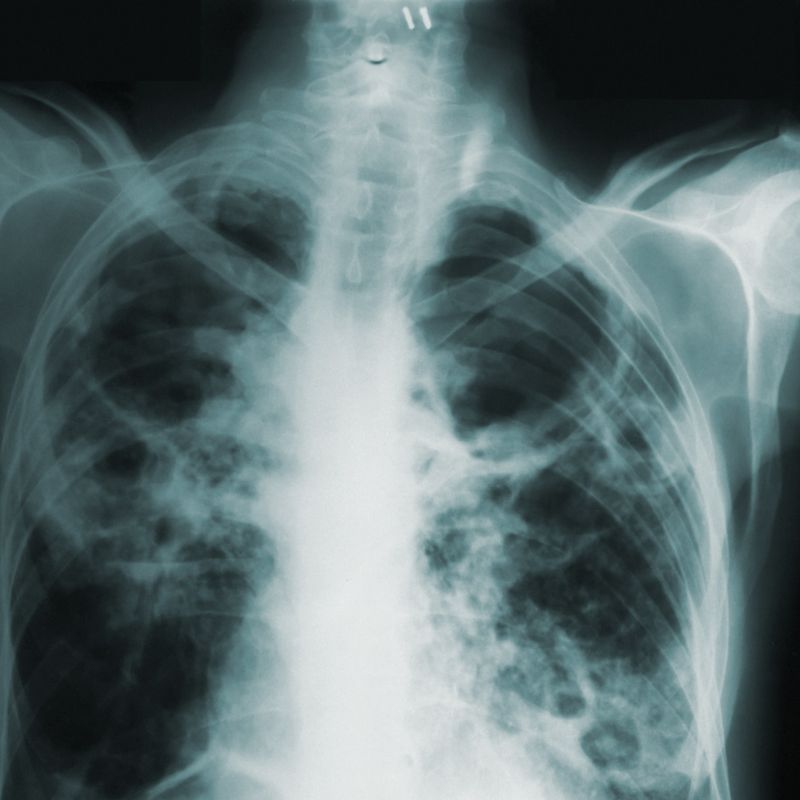

Los rayos X son un tipo de radiación electromagnética similar a la luz visible. Sin embargo, a diferencia de la luz, estos rayos tienen mayor